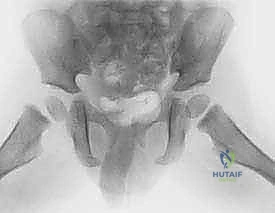

- الفحص السريري الشامل: تقييم حالة الأعصاب والأوعية الدموية في الطرف المصاب.

- الأشعة السينية (X-rays): صور أمامية وجانبية للحوض والورك لتأكيد الكسر وتحديد نوعه.

- الأشعة المقطعية (CT Scan): يطلبها الدكتور هطيف في الكسور المعقدة والمفتتة لبناء تصور ثلاثي الأبعاد يساعد في التخطيط الدقيق للعملية الجراحية.